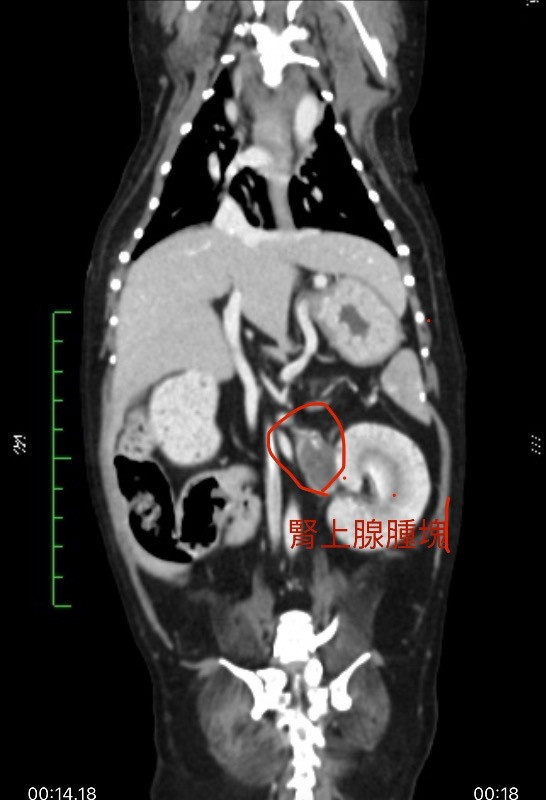

妍兒 2025-09-29 她剛開完拆膽䉴手術 跟拆脾藏 過了五天出院⋯ 愛犬睡到凌晨三點走了 請問是腎上腺腫瘤破裂造成休克嗎? 他的醫生是這樣說!還說腫瘤不能開刀她13歲了 、還有腫瘤位置也不能開刀旁邊有大血管! 真的好難過 懇請有醫生知道能跟我說ㄧ下 腎上腺腫瘤破裂真的會造成死亡嗎? 姚勝隆 院長 2025-10-07 治療中或術後的動物,建議與主治獸醫師多討論,只有主治獸醫師最清楚寵物的病況。 1 分享–– 我也要提問